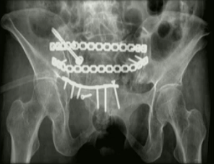

目前骨盆前环骨折的固定方式主要有四种:钢板、螺钉、外固定支架、内固定支架(即Infix技术)。由于前三种手术技术存在一定局限性,学界一直在寻找一种更加安全可靠、操作简单的骨盆前环骨折固定技术。

2009年:Kuttner研发了一种基于经皮下骨盆前环内固定技术(internalfixator, INFIX),用于耻骨联合分离的复位与固定,后续所有24例患者,术后复查复位均良好。

2012年:Vaidya详细阐述并明确提出了Infix的观念:Internal fixator适用于前环损伤的骨盆骨折,尤其是肥胖、伴有膀胱损伤的患者。

该手术在皮下操作,在超髋臼区进行固定稳固,具有力臂短、把持力强、操作简单、创伤小、容易取出、允许早期锻炼及负重、不需要考虑血管神经等优点,更符合BO原则。